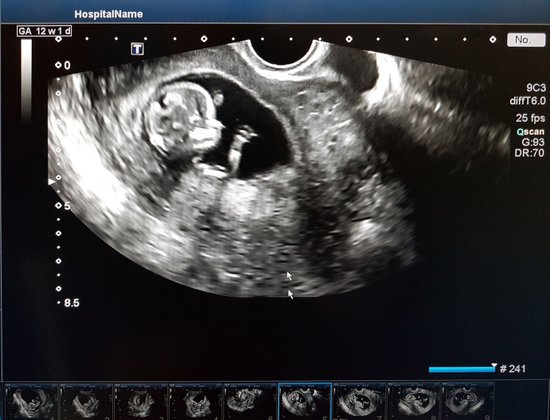

Wie wächst das Baby im 2. Trimester?

Im zweiten Schwangerschafts-Drittel geht es rund: Die Sinne entwickeln sich weiter, das Baby trainiert im Bauch fleißig Kickboxen und das Geschlecht ist klar erkennbar. Was noch? Hier kommen die Entwicklungsschritte des Fötus von SSW 13 bis SSW 28 im Überblick. Möchtest du noch mehr Details zur Entwicklung wissen, klicke einfach auf die jeweilige Woche.

Vom Embryo zum Fötus – die Entwicklung im zweiten Trimester als Tabelle:

SSW | Entwicklung vom Embryo zum Fötus | Durchschnittliche Größe Scheitel-Steiß-Länge | Durchschnitts-Gewicht |

In SSW 13 nimmt der Embryo die Form eines Babys an, erste Reflexe sind vorhanden. Die Stimmbänder entwickeln sich. | 6- cm | 23 g | |

Neben den Haaren wachsen nun in der 14. SSW die Augenbrauen. Die Käseschmiere schützt den kleinen Körper, Gesichtsmimik entsteht. | 8 cm | 40 g | |

Der Nacken bildet sich weiter aus, sodass der Kopf nicht länger auf der Brust liegt. Die Zunge entwickelt um SSW 15 Geschmacksknospen. | 10 cm | 70 g | |

Das Geschlecht ist in SSW 16 deutlich erkennbar. | 11 cm | 100 g | |